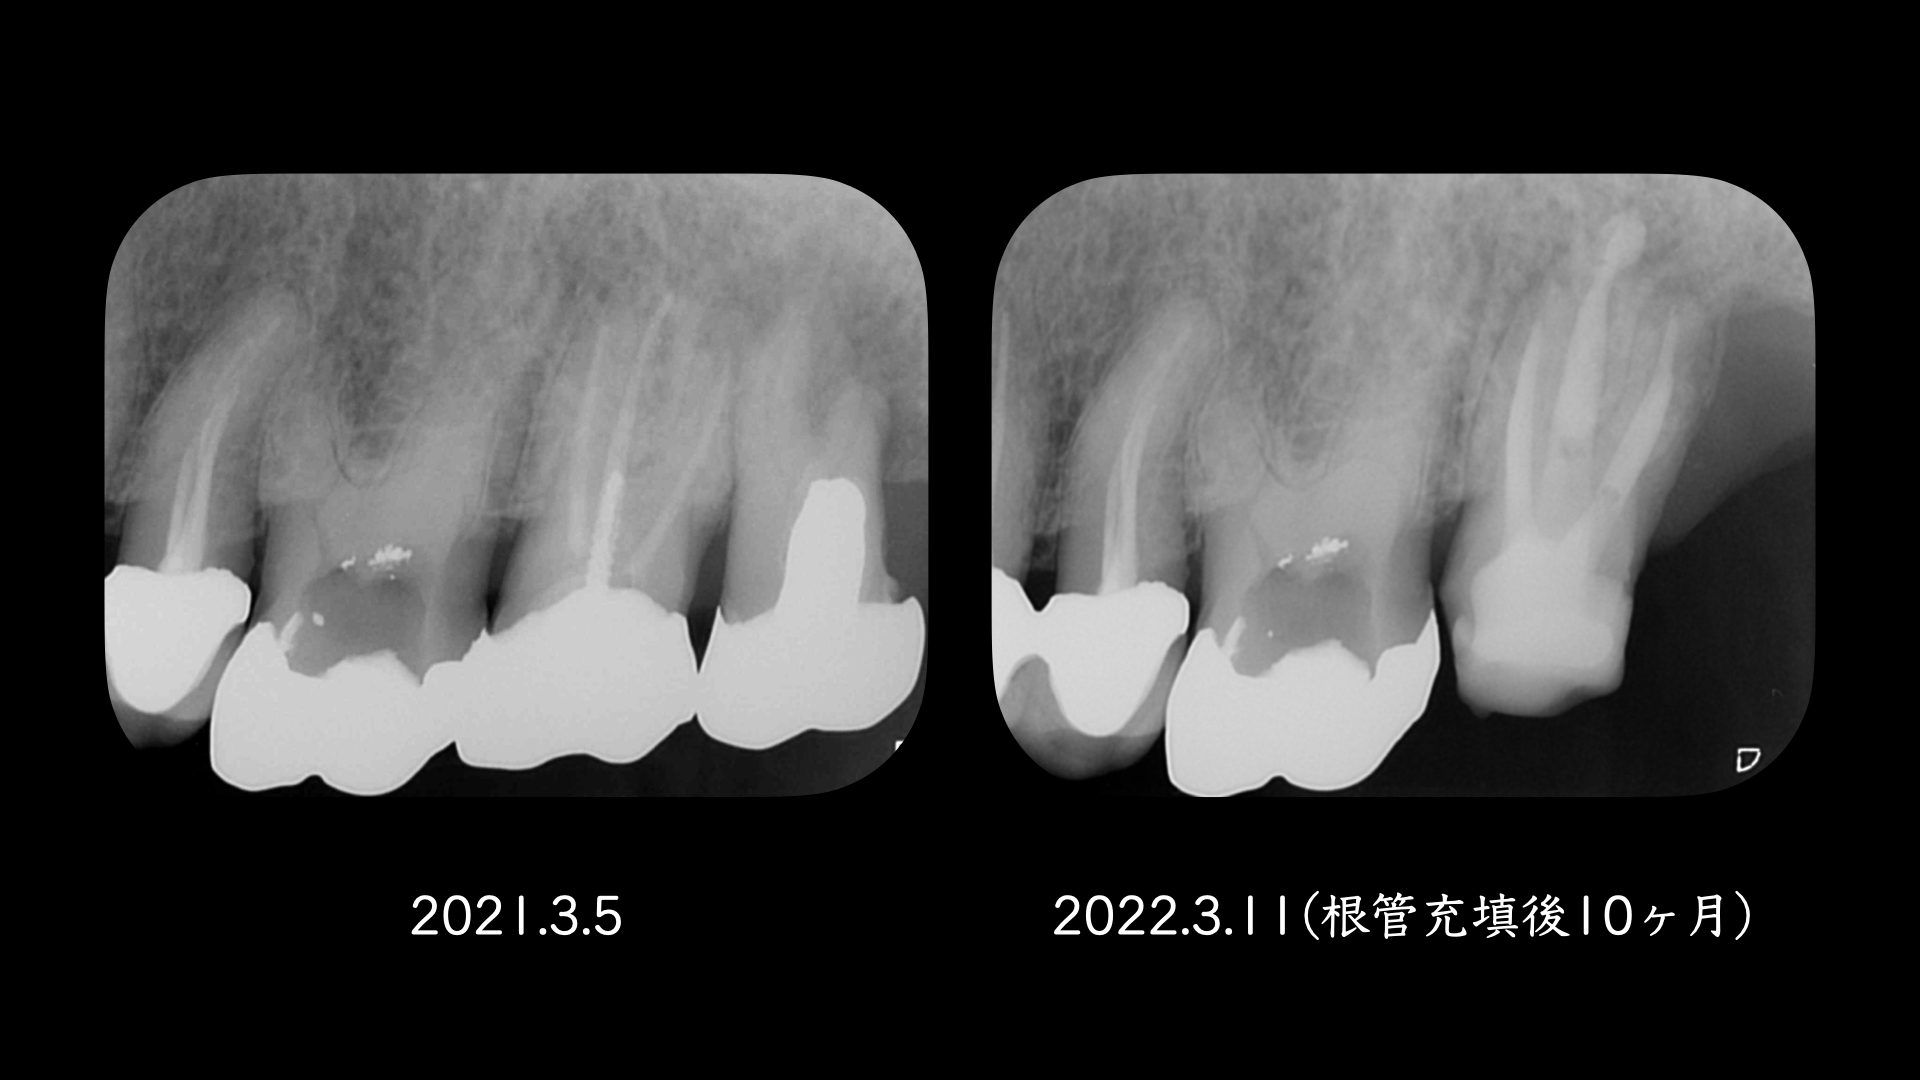

右の画像のCT上で根尖部にかなり大きな透過像があります。

根管治療はマイクロスコープを使用し、根管内は綺麗になった。と判断したので2回でMTAセメントにより根管充填をおこないました。

噛み合わせの反対側(下顎)はインプラント治療をおこなっており、経過をみていましたが全く変化がありませんでした。